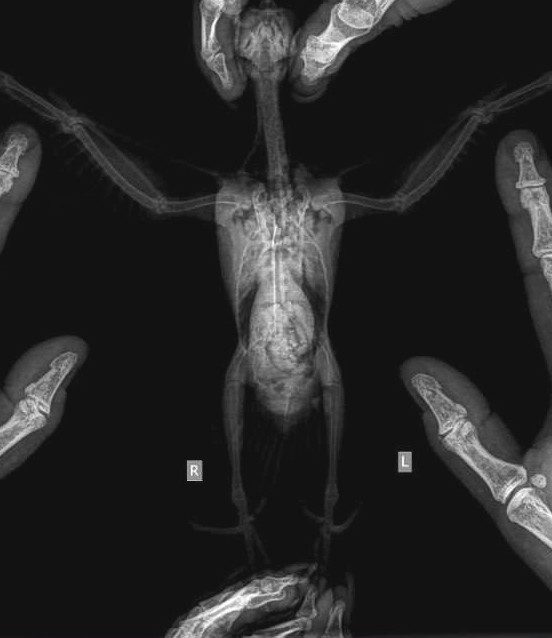

Врач по разговору мне показалась вполне толковой, насколько я могу судить по своему опыту. Она говорила правильные вещи про содержание, питание, правильно называла дозировки лекарств - когда содержишь корелл достаточно долго и погружаешься в тему, дозировки самых часто назначаемых препаратов (типа обезболивающих) уже помнишь наизусть. На рентгене она переломов не увидела, предположила просто ушибы. Но рекомендовала пока ограничить ему подвижность.

Уже приехав домой и посмотрев рентген, я увидела, что раскладка сделана странно, да и то, что наш птенец совсем не мог ходить даже после обезболивающего, меня беспокоило. Поэтому на следующий день я всё-таки отвезла его на приём к одной из наших постоянных докторов. Та сделала новый рентген и, судя по всему, провела мини-консилиум в мессенджере, после чего сказала: да, похоже, что есть переломы обеих голеней по типу "зелёной ветки". Поясню: это когда кость повреждена с одной стороны, а вторая сторона осталась целой - как если ломаешь молодую, ещё гибкую ветку дерева, она надламывается, но не разделяется на два отдельных фрагмента. Сказала, это частый вид травм у молодняка, связанный с тем, что масса тела прибывает быстрее, чем крепнет костно-связочный аппарат, и такая травма может возникнуть практически из ничего. Я, в свою очередь, грешу на то, что этим птенцам давала кальций другой фирмы, более дешёвый - может, он был некачественный...

Такие переломы непросто увидеть на снимках, и точная раскладка имеет большое значение. Обычно для рентгеновских снимков птиц раскладывают в четыре руки. Первая врач делала это в одиночку - она работала без ассистента. И конечно же, раскладка получилась кривая. Думаю, она зря никого не позвала помочь. Мне доводилось помогать с раскладкой на рентгене, но она меня видела впервые, и недоверие ко мне как к потенциальному помощнику тоже можно понять.